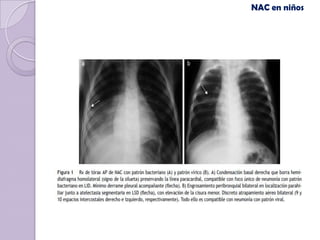

NAC en niños

(Khamapirad y Glezen )

Torres F, Chiolo M, González N, Durán P. Capacidad para predecir etiología con la radiografía

de tórax en niños hospitalizados con neumonía. Archivos argentinos de pediatría. 2006 Abr.